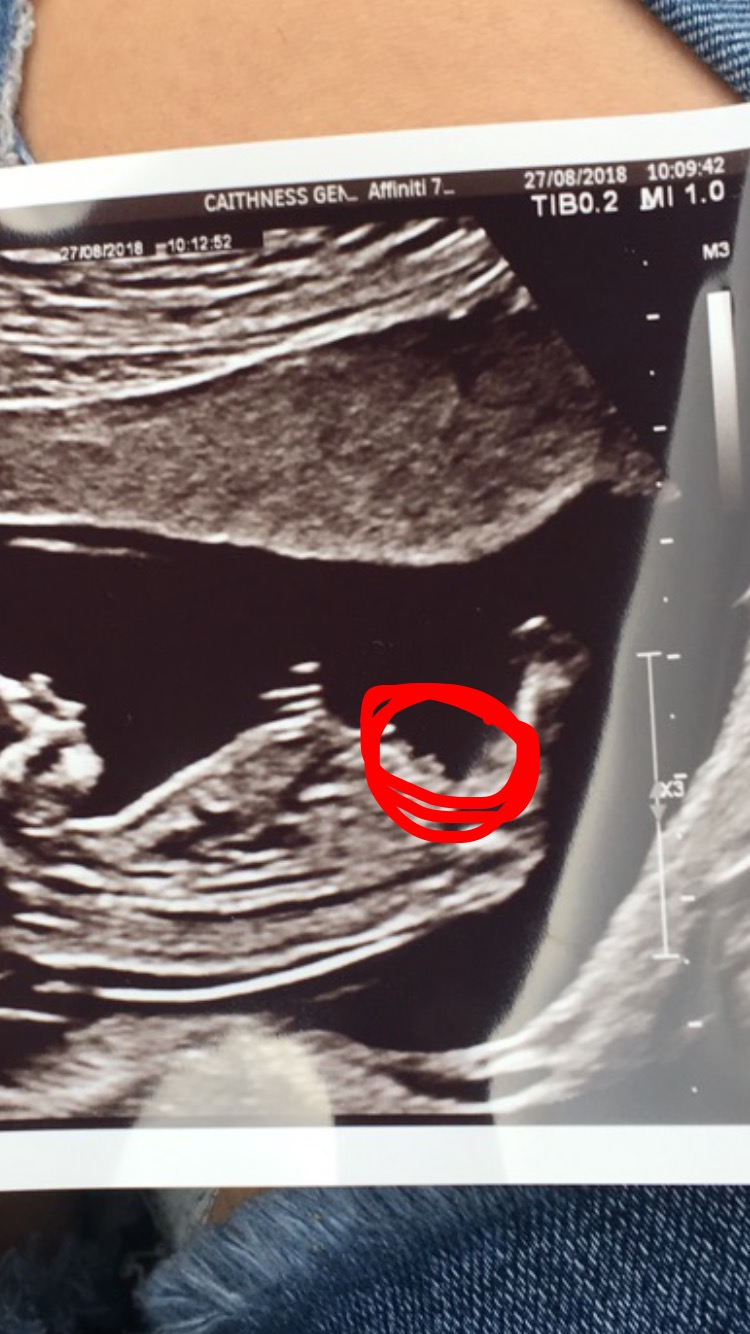

Is this the nub I have circled in my scan picture? I have no idea what I’m looking for. If so boy or girl?? Any help would be great thanks Attachment 40236

No that doesn't look like the nub as it's up too high. I don't really even see the nub in this pic.